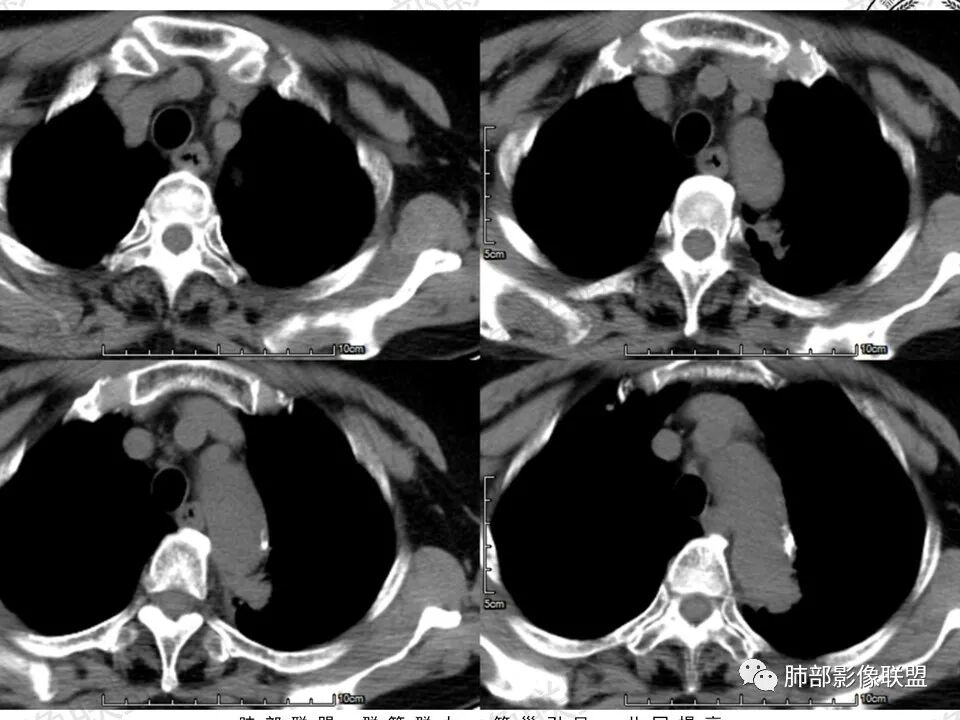

临床,眼科入院常规,肺部无症状,慢性炎症或恶性偷袭。视物变形,黄斑裂空可以解释,颅内不一定有问题,常规眼部ct,以防万一。定位,肺内血管进入,外缘毛糙,有肺纹进入,肺内的可能大。影像:    良性征像, 1、 病灶紧贴主动脉的细、长条状,炎性的王牌。2  、有直边、多边征 3、 矢状位略成梯形,垂直主动脉弓。  恶性征像较多,但多位低权重征像部分似是而非:1 主动脉弓后缘动脉壁似有侵袭 2  斜裂有轻度收缩 3 内上似见一个月牙铲 4 实性病灶周围有境界清晰的磨玻璃影  5 有小叶间隔阻挡现象 6 血管造影征?7 病灶略有膨隆 。中立征像:持续高强化,可以见于1 腺癌 、2 纤维类肿瘤 3肉芽肿病变。综上 1 腺癌第一(伴粘液腺)2 炎性肉芽肿待除外

马春平(张家港市一院胸外科):沿着支气管、肺动脉或主动脉、心缘、膈肌旁生长的腺癌形态会千奇百怪,抓住最重要的一条:找周边沿腺泡囊生长、边界较清的磨玻璃灶。

Coke with ice:病例收缩力偏弱,有磨玻璃,有牵拉支气管扩张,明显强化。可疑栽桩。符合实体型腺癌的表现。需要考虑到粘液腺的可能性。

张勇:边界清晰的磨玻璃影+支气管扩张是很强烈的恶性

马春平(张家港市一院胸外科):大伙要牢记一点,腺癌的病程相对比较长,破坏力小,遇到阻碍短时间越不过,侵犯间质后形成收缩力,再遇到支气管、血管就形态各异,向各个方向的生长速度也不一样。

如果再合并无临床症状的阻塞性肺炎、局限性肺不张,密度和强化变化会更复杂一些